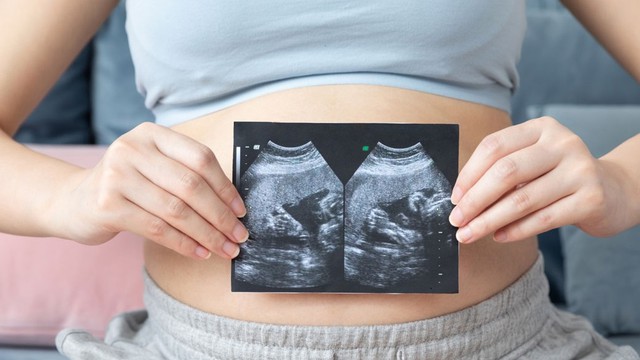

Nhiều mẹ bầu sau khi thăm khám và được chẩn đoán bị tụ dịch màng nuôi 27mm thường khá lo lắng. Bài viết dưới đây Long Châu sẽ giúp bạn hiểu rõ hơn về tình trạng này và những lưu ý quan trọng.